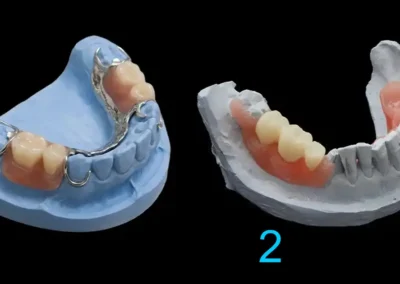

Prótesis parcial acrílica

Puede ser razonable cuando se necesita una solución removible simple o una etapa transitoria bien controlada. En ciertos casos cumple adecuadamente su función, pero no ofrece el mismo nivel de estructura ni el mismo comportamiento que otras alternativas mejor soportadas.

Prótesis parcial metálica

Suele ser una alternativa más firme y más precisa cuando los dientes remanentes permiten un diseño más estable. No se indica por lujo ni por moda, sino cuando el caso realmente se beneficia de una estructura con mejor comportamiento funcional.